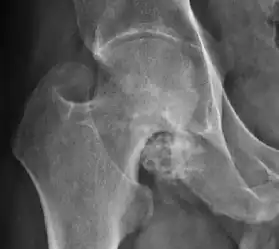

Plain radiography allows us to categorize the hip as normal or dysplastic or with impingement signs (pincer, cam, or a combination of both). Besides these, pathologic processes like osteoarthritis, inflammatory diseases, infection, or tumors can also be identified (Figure 1).[1]

Figure 1.

There are other pathological conditions that can affect the hip joint and radiographs help to make the appropriate diagnosis. Acute bacterial septic arthritis can be diagnosed by radiographs when a fast regional osteoporosis and destructive monoarticular process develops (Figure 1(f)). In case of tuberculous or brucella arthritis it is manifested as a slow progressive process, and diagnosis may be delayed.[1]

Synovial chondromatosis can be confidently diagnosed by X-ray when calcified cartilaginous chondromas are seen. However, other synovial proliferative processes, such as pigmented villonodular synovitis, require MRI for accurate diagnosis, although noncalcified synovitis can be suspected in radiographs by indirect signs, such as soft tissue swelling and/or erosions in the femoral head, femoral neck, or acetabulum (Figure 7).[1]